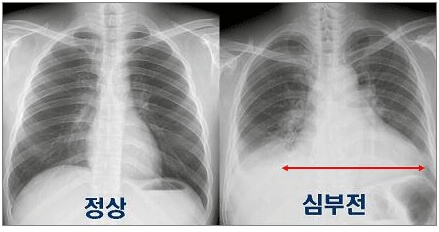

심부전은 심장이 완전하지 않은 상태, 즉 심장 기능에 이상이 생겨 몸 구석구석으로 산소ㆍ영양분이 포함된 혈액을 충분히 공급하지 못하는 심장 기능 상실을 뜻한다. 그러나 심부전은 그 위험성이 제대로 알려져 있지 않은 편이다.

심부전이 발생하면 폐에 혈액이 고이는 폐부종이 나타나므로 호흡곤란을 가장 흔히 겪는다. 처음에는 움직일 때만 숨이 차지만, 심해지면 가만히 쉴 때나 잠을 잘 때도 숨이 차는 증상이 나타난다.